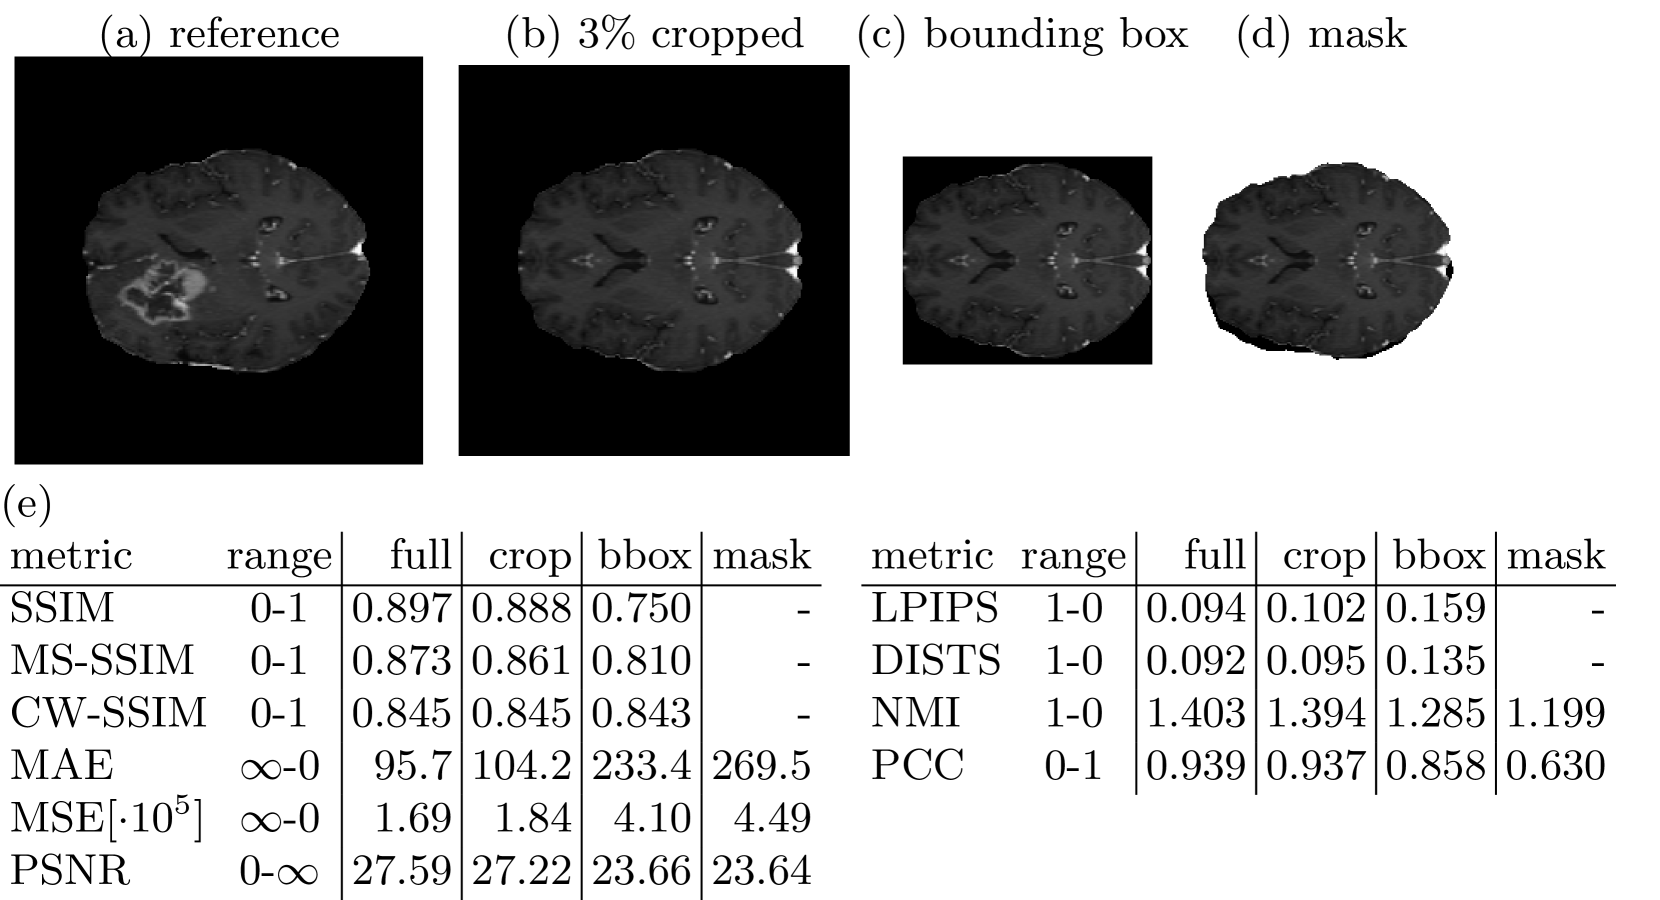

Figure 3: An example reference image (a), its by 3% cropped version (b), its by a bounded box cropped version (c) and an exactly foreground masking version (d) are shown. Mean similarity scores over 100 images are listed in (e). With less identical background included in the calculation, the assessed similarity strongly decreases.

3.3 Pitfall 3: Background, Foreground and Region of Interest Similarity

Medical images are often acquired to detect a pathological condition in a very specific location in the human body. Even though the field of view can be narrowed, medical images often picture neighboring structures and a large fraction of background, that are not of interest for diagnosis. Similarity of medical images is especially relevant for a limited region of interest, i.e. a possible lesion or tumor, a specific organ, bone, muscle or tendon. Pictures of brain tumors are perceived more similar, if they show the same type of tumor at the same location, rather than the same texture of healthy brain tissue or even the same background intensity. Therefore, it is important to be able to mask out rather irrelevant parts of an image and to evaluate specified regions of interest separately. Fig. 3 shows similarity metric scores for increasingly cropped brain images, where the test image consists of the upper hemisphere of the brain in the reference image and the lower half of the image is replaced by a mirror of the upper hemisphere. In most cases of the BraSyn Dataset this leads to either two or no tumors in the test image opposed to exactly one tumor in the reference image. However, when background composes a large part of the image to be evaluated, similarity metric scores appear very high. With decreasing background the similarity metric scores also noticeably decrease.